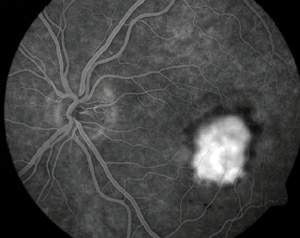

Picture of the fundus showing intermediate age-related macular degeneration. | |

يأمل الباحثون تطويرَ معالجات جديدة تستطيع إبطاء تقدم التنكس البقعي أو إيقافه. إن المَعْلم المميز للتنكّس البُقْعي هو فقدان الرؤية المركزية، غير أن مظهر الشبكية يختلف على نحو كبير من مريض إلى آخر. وفي معظم الأحيان، يرتبط المرض البقعي عند المسنين ـ الذي يُدعى الاعتلال البقعي المتعلق بالعمر age-related maculopathy (أو اختصارا ARM) ـ بفقدان في خلايا الظهارة RPE. فعندما يُنظر إلى الشبكية عبر منظار العين ophthalmoscope يظهر فقدان تلك الخلايا على شكل باحات غير مصطبغة، أو مصطبغة ولكن على نحو غير منتظم. ويمكن تعرف فقدان خلايا الظهارة RPE على نحو أكثر دقة بالتصوير الفلوروسيني (اللاّصِف) للأوعية fluorescein angiography، وهو تقنية تمكِّن أطباء العيون من رؤية الأوعية الدموية للعين بحقن مركب فلوروسيني في تيار الدم. ففي العين السوية يُرى الصباغ الفلوروسيني بسهولة في أوعية الدم الدقيقة ضمن الشبكية، غير أنه لا يُرى ـ أو يُرى بصعوبة كبيرة ـ في الأوعية المشيمانية الأكثر انتشارا؛ لأن هذه الأوعية تقع خلف الاصطباغ الثقيل للظهارة RPE. أما في عين مصابة بالاعتلال ARM فيظهر الصبغ داخل الدورة المشيمانية في أي باحة فقدت خلايا من الظهارة RPE.